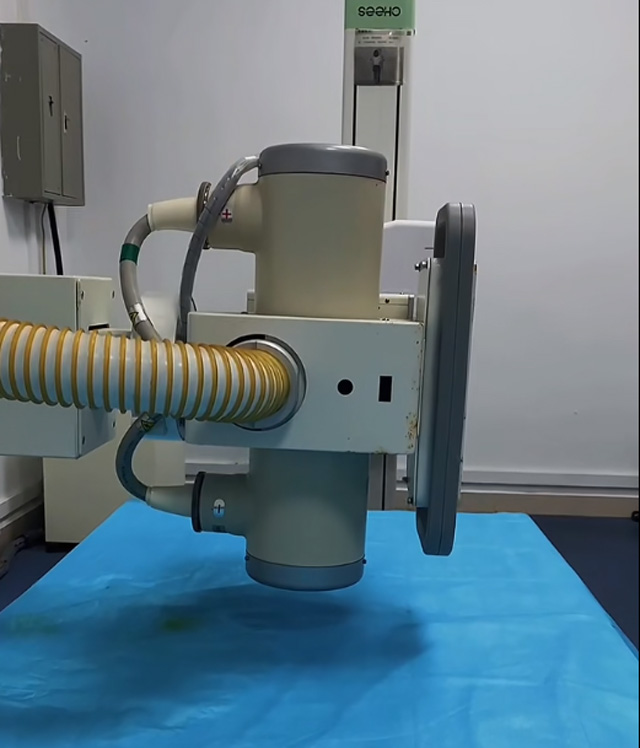

传统的X线检查它需要把胶片拿去冲洗才能出来结果,平床DR机不一样,即便是多种部位的检查可以拍摄身体的各个部位,很快的可以直接传输到电脑去。几分钟就可以出结果报告减少了等待时间。那么平床DR有什么防护措施呢?头部防护有铅帽,这个帽子有点重量的,戴上它可以更好的保护儿童的头部部位。还有围脖、围裙、铅服,都是比较重的。这样才能保护好儿童的各个身体部位。

这个辐射到底对儿童有没影响呢?其实影响不大的,预测孩子的骨龄是对身高的评估。怎样监测,儿童在正常生长发育的过程中,随着年龄的增加。骨骼线会逐渐的钙化直至完全骨化,骨骼线闭合。骨龄是各个年龄骨的成熟度,正常情况下骨骼的年龄,和实际的年龄不应相差正负超过一岁。提前或者落后太多都是不正常的。用儿童的左手腕拍一张DR片来测骨龄,通过影像来观测儿童骨骼生长发育情况。预测儿童的生长发育潜力。这个骨龄监测是比较准确的。

还有精准骨骼线检查的位置在膝关节,通过DR拍片可以明确的看到骨骺线的状态。这就是为什么检查了手掌的骨骼线还有检查膝关节的。手掌的骨骼线闭合了,也不一定代表不能生长了,通过精准的骨骼线检查,判断儿童是否有长高的可能。膝关节骨骼线未闭合就可以进行身高的干预治疗。